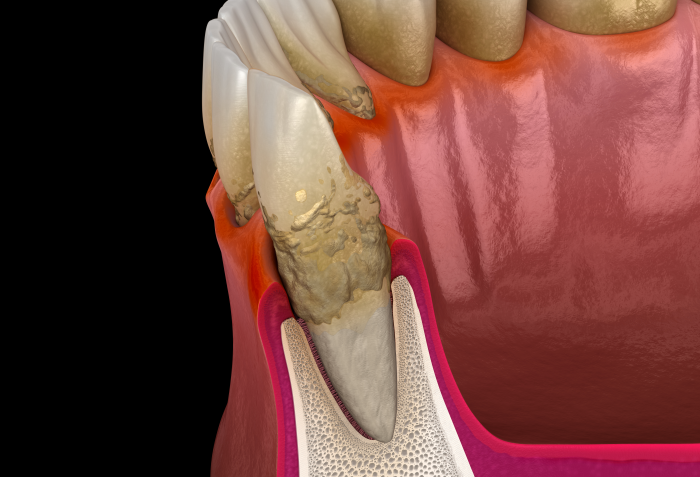

하지만, 치은연하를 방치하게 되면

세균이 점차 잇몸 속 깊이 침투하기 때문에

잇몸이 내려앉게 만드는 것은 물론이며,

심각할 경우 잇몸뼈를 녹여 치아를

지탱하는 힘을 잃게 되어 발치를

진행해야 할 수도 있는데요.

뿐만 아니라 치은 연하는 잇몸을 타고

혈관을 통해 다른 신체기관으로 이동하여

부정적인 영향을 끼치기도 해서

치료 시기를 놓치지 않고 제때에 치료

할 수 있도록 신경을 써주셔야 합니다.